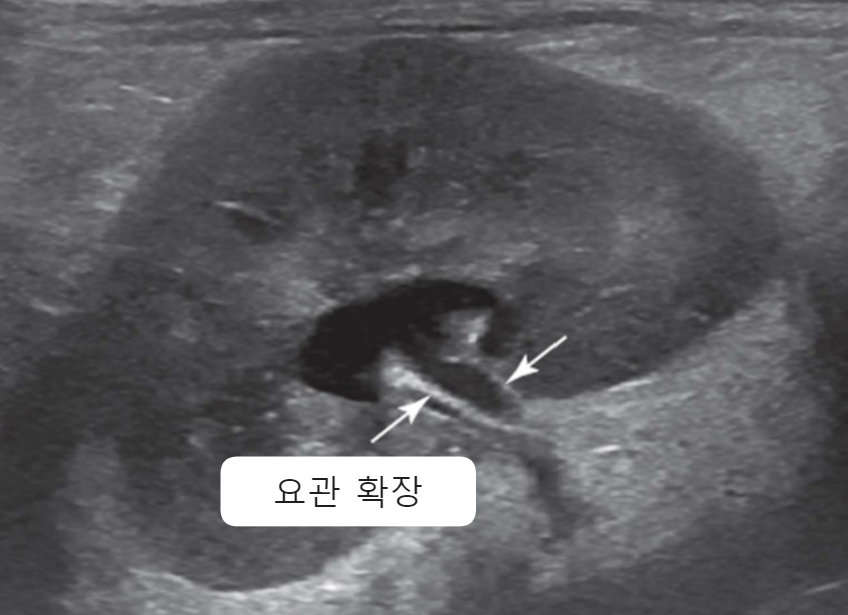

| Ultrasonography (Abd) | _Pyelonephritis |

|---|---|

![]() | - ๋ํ์ ์ผ๋ก ์ผ์์ ์ธ ์ฝฉํฅ ๋น๋ (renal pelvic dilation) - Ureteral dilation (์๊ด ํ์ฅ) - Blunting of the renal papilla (์ฝฉํฅ์ ๋์ ๋ํ) - Echogenic debris (๋ด๋ถ์ ๊ณ ์์ฝ์ฑ ์ํด) * ์ ์ฐ์ ์ผ์ธ๋ฐ ์ฝฉํฅ์ด ์ถ์๋์ด ์์ผ๋ฉด, CKD๋ ๋ง์ฑ ์ ์ฐ์ ์ผ์ ์์ฌํด๋ณด์. + Bacterial culture : pyelocentesis(์ ์ฐ์ฒ์)๋ ์ค์ง์ ๊ฑด๋๋ฆด ์ ์์ผ๋, ๋ฐฉ๊ด sampling๋ถํฐ ์๋ |